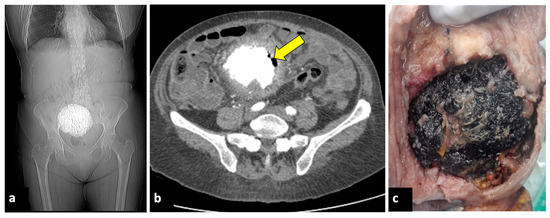

Asymptomatic Cervical Amputation Caused by Uterine Torsion in a Non-Gravid Woman

by Milan Stefanović, Predrag Vukomanović, Ranko Kutlešić, Milan Trenkić, Vanja Dimitrov and Aleksa Stefanović

J. Clin. Med. 2024, 13(23), 7356; https://doi.org/10.3390/jcm13237356 - 3 Dec 2024

Background: Uterine torsion represents a rare condition that may occur during pregnancy or in non-gravid women. This condition is difficult to diagnose, since there are no specific signs besides abdominal pain. Thus, most of the cases are not diagnosed correctly before a surgical procedure and may result in complications and poor outcomes. Methods: We present the first case of uterine torsion of 1080 degrees counterclockwise, with asymptomatic cervical amputation. Results: The intraoperative finding was a uterus that was twisted 1080 degrees around its longitudinal axis, a large fibroid > 15 cm, a large ovarian tumor > 15 cm, and a missing cervix. Upon further inspection, the cervix was found, completely separated from the body of the uterus. After the surgery, the patient remained stable, and her postoperative course was uneventful. She was discharged on the eighth postoperative day. No complications were detected 2 months after the surgery. Conclusions: This specific case is extremely unique, being the only one in searched literature with a 1080° torsion and an amputated cervix. Uterine torsion, especially in postmenopausal women, is a highly rare condition and is difficult to diagnose, with potentially serious outcomes. Any doubts should be assessed as quickly as possible and be dealt with appropriately. If possible, MRI and CT scans could be of great help in differential diagnosis. Full article

Figure 1